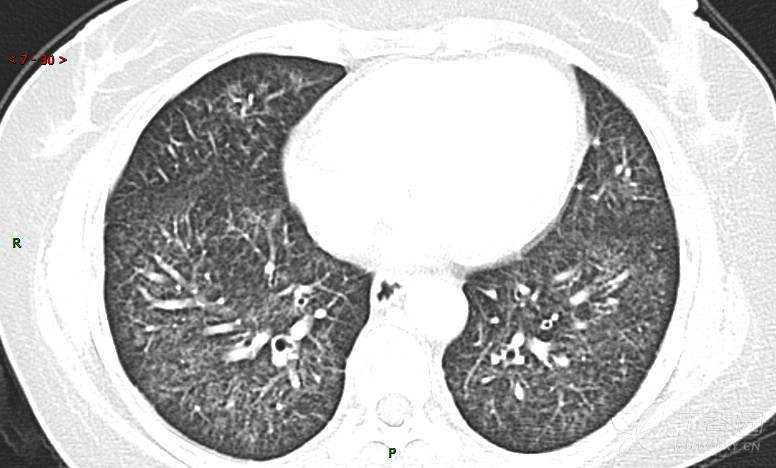

肺内弥漫性网状结节影,PET-CT却无阳性病灶,这是?(附其他2例链接)

女性,58岁,阵发性咳嗽2月,加重1月。

患者于2月前无明显诱因出现咳嗽,以阵发性干咳为主,接触冷空气后咳嗽明显,偶咳少量白色泡沫样痰,咳嗽剧烈时感憋喘,无发热、盗汗,无头痛、头晕,无胸痛、咯血,无恶心、呕吐,无腹痛、腹泻,无尿频、尿痛等不适,于当地医院给予肌注及静脉药物治疗,具体药物名称不详,效果欠佳,近1月来患者咳嗽频率较前增加,咳嗽剧烈时感双侧季肋区疼痛不适,10余天前出现发热,体温在38℃左右,伴畏寒、寒战,无头痛、头晕,无纳差、乏力等不适,药物治疗后体温降至正常,仍阵发性咳嗽,今为求进一步诊治,就诊于我院急诊,因呼吸内科暂无床位,急诊门诊以“肺间质病变”收入急诊留观室,给予“抗感染、止咳”等对症支持治疗后,今日以“肺间质性病变”收入我科,患者自本次发病以来,神志清,精神可,饮食尚可,睡眠一般,大小便正常,体重较前无明显变化。